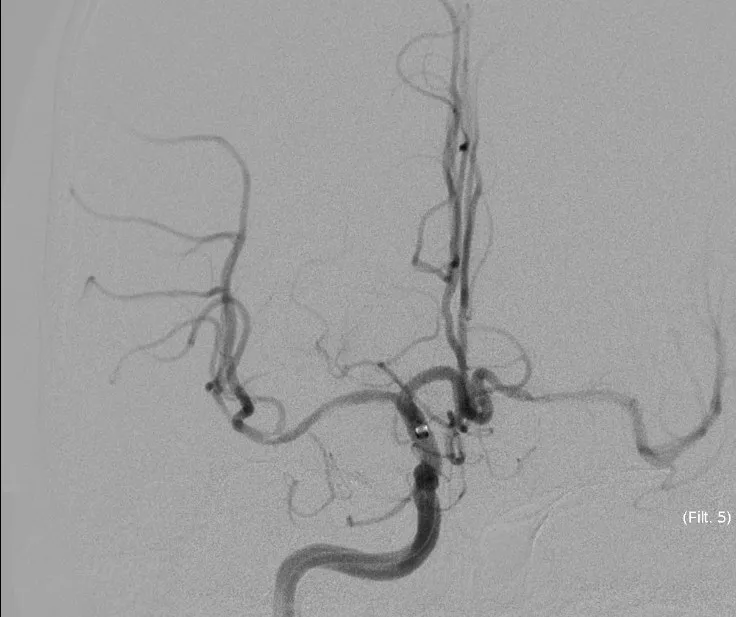

立即DSA(08-03日 13:24分)

5MIN后

5MIN后

赛诺 2.0*15mm球囊扩张

5MIN后

赛诺 2.0*15mm球囊扩张

5MIN后

10MIN后